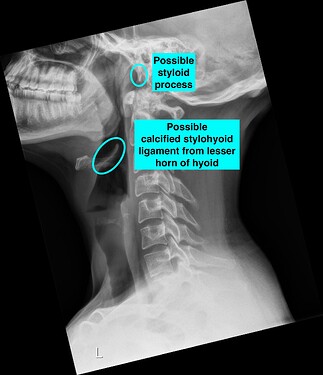

I think your left styloid is visible, but it looks very short. What @Jules thinks is a curved greater horn of your hyoid, I think might be calcification of your stylohyoid ligament coming off the lesser horn of the hyoid. It’s simply not clear enough in the image to tell for sure.

I annotated a couple of the images to show you what I’m guessing might be abnormal. You must remember we aren’t doctors so nothing we tell you can be used for an official diagnosis.